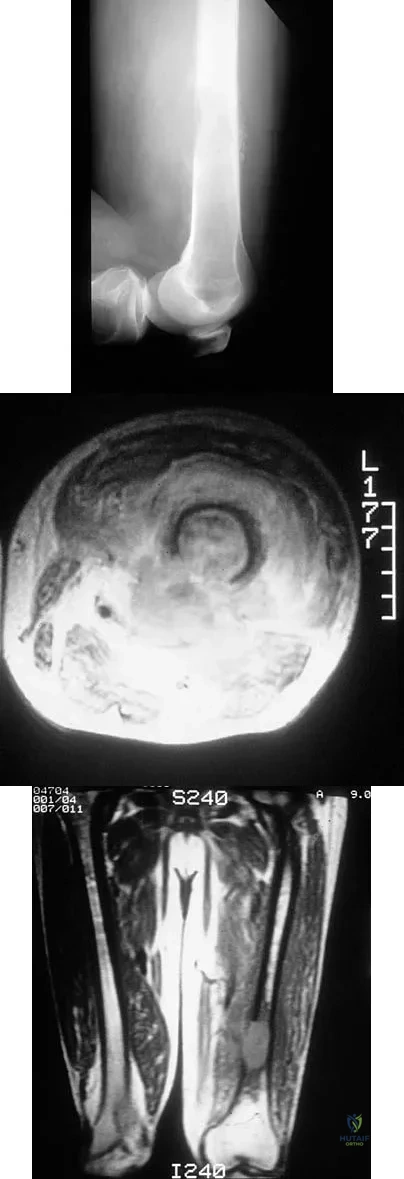

Figures 48a through 48c show the lateral radiograph and MRI scans of a 60-year-old man who has had pain in his thigh for 1 month. The next most appropriate step in management should consist of

Explanation